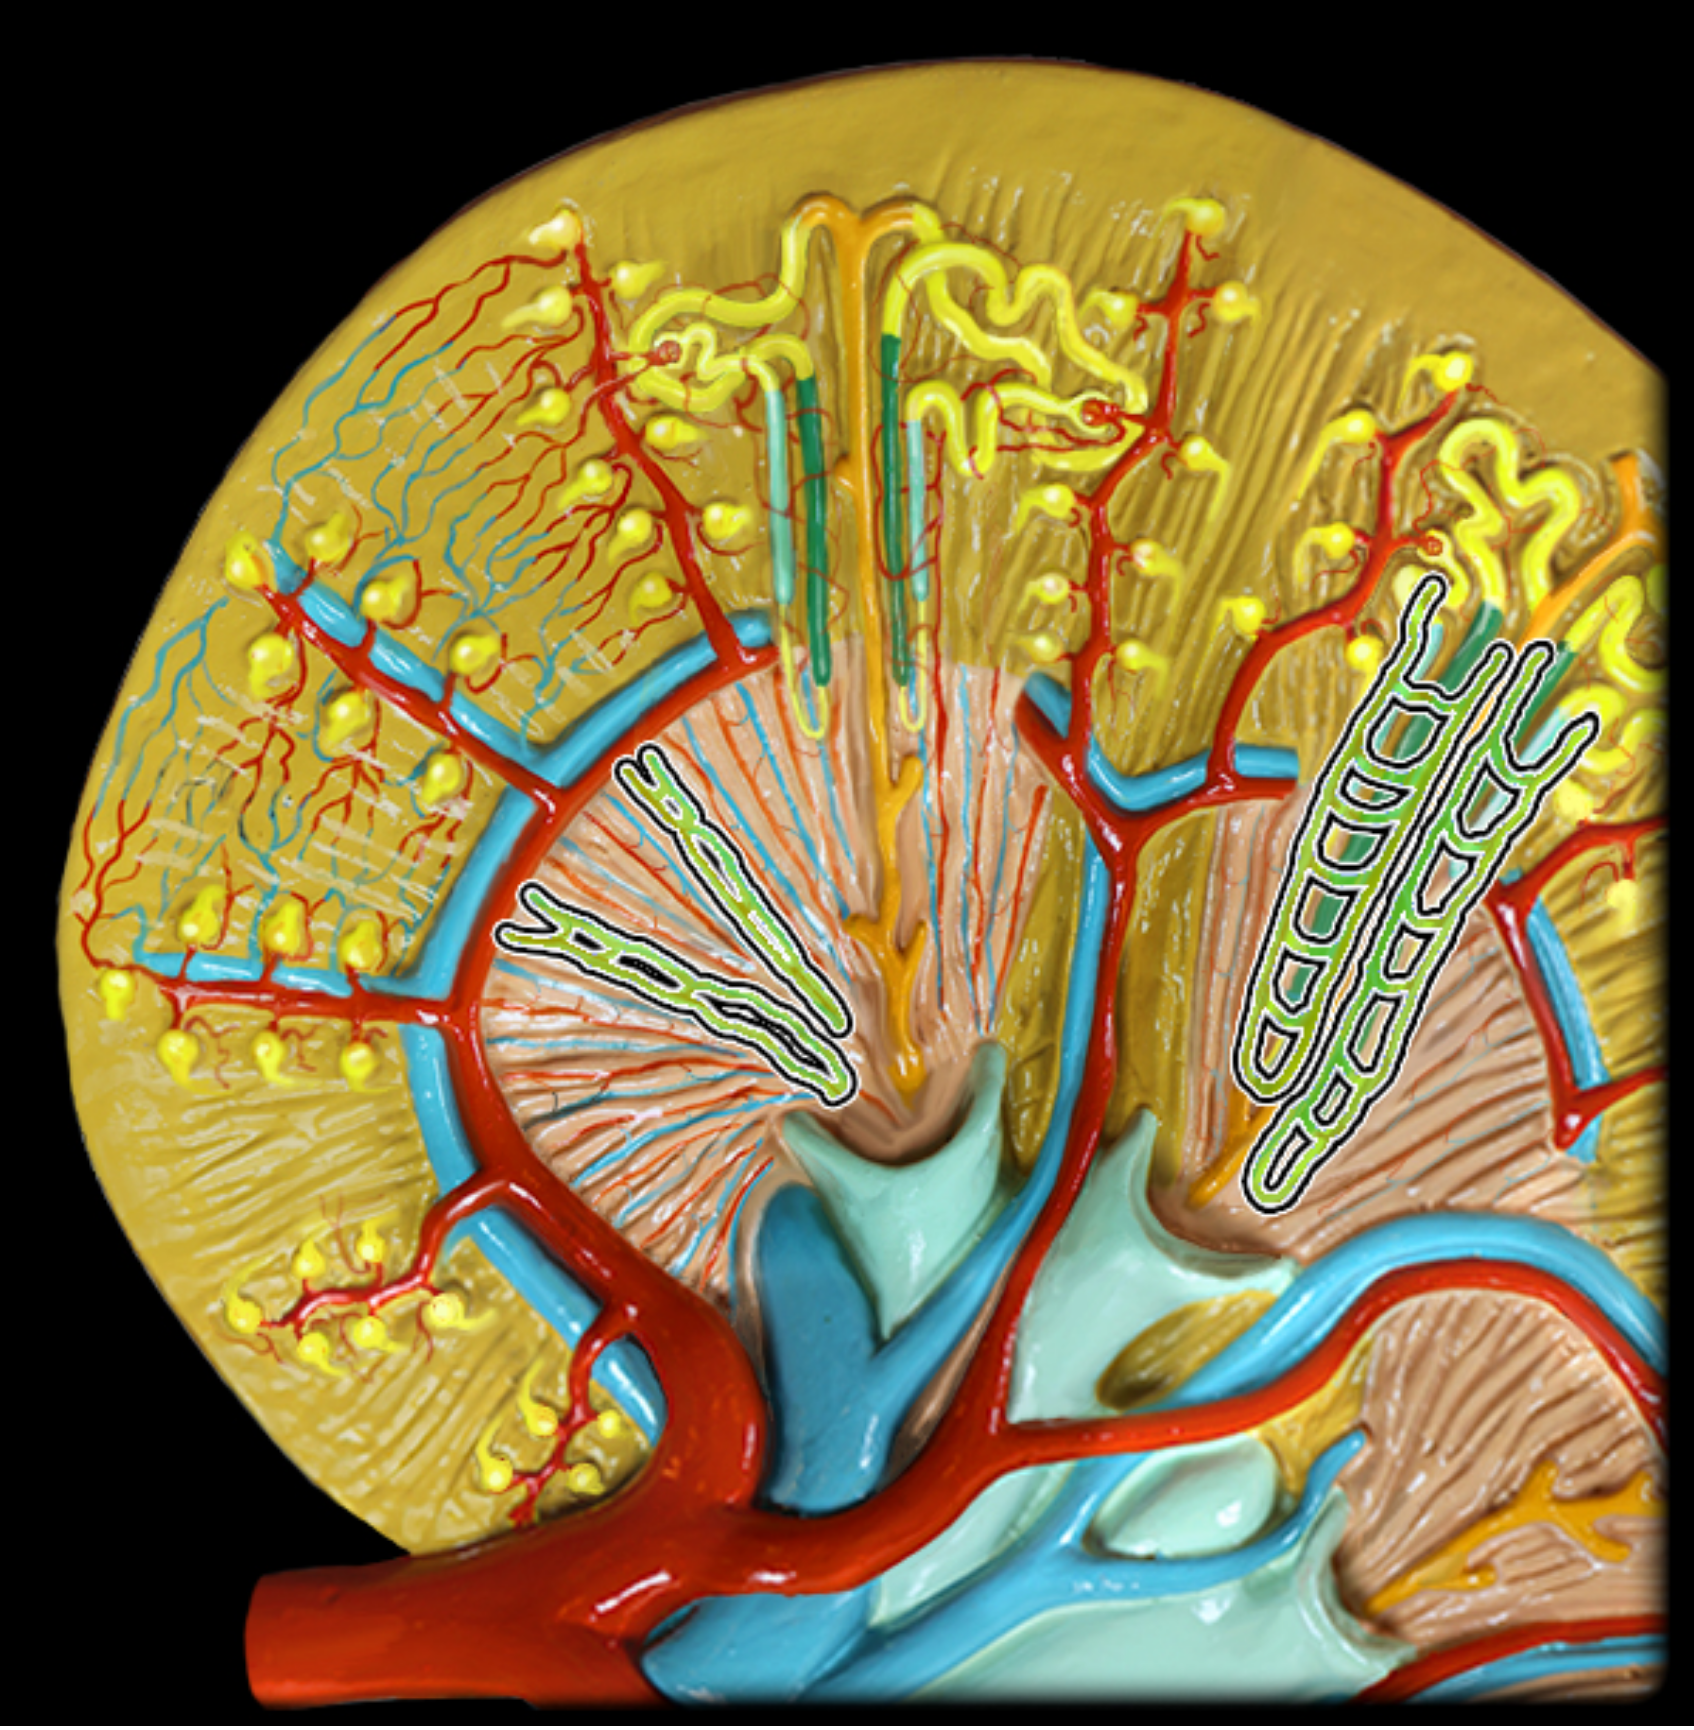

Peritubular capillaries

vasa recta

Renal corpuscle

bowmans capsule + glomerulus